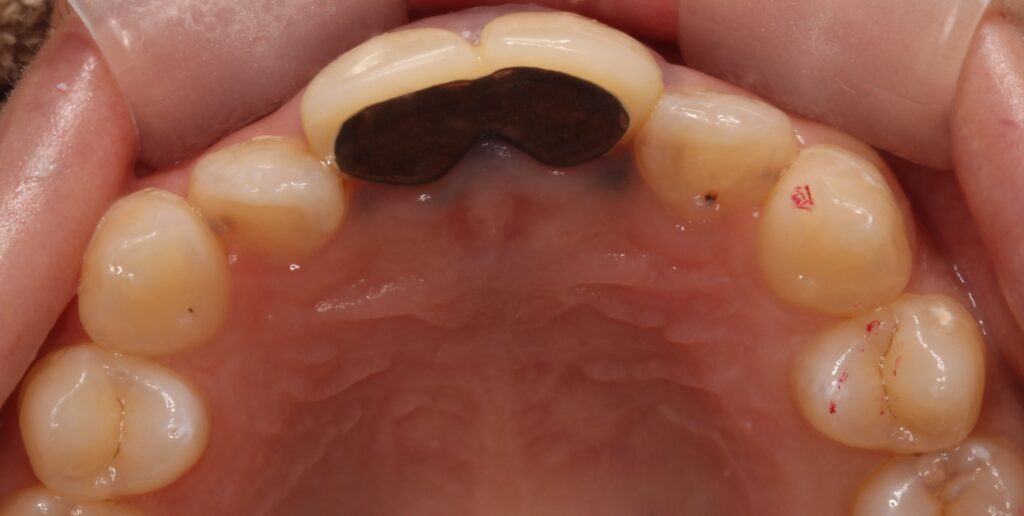

裏側を見ると。。。

黒く見えるのが金属で、酸化して黒く変色しています。

現在でも全国どこでも毎日使われる、保険適応内の治療方法です。